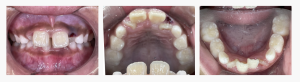

【上顎前突・叢生・口唇閉鎖不全】早期矯正|7歳男児|…

みなさんこんにちは。 兵庫県明石市魚住町、西江井ヶ島駅から徒歩6分、 こどもの矯正に強い明石市の歯医者、ハローこどもファミリー歯科です。 今回は、「前歯が出ているのが気になる」というご相談をきっかけにスタートした、 7歳男の子の症例をご紹介します。   来院のき…